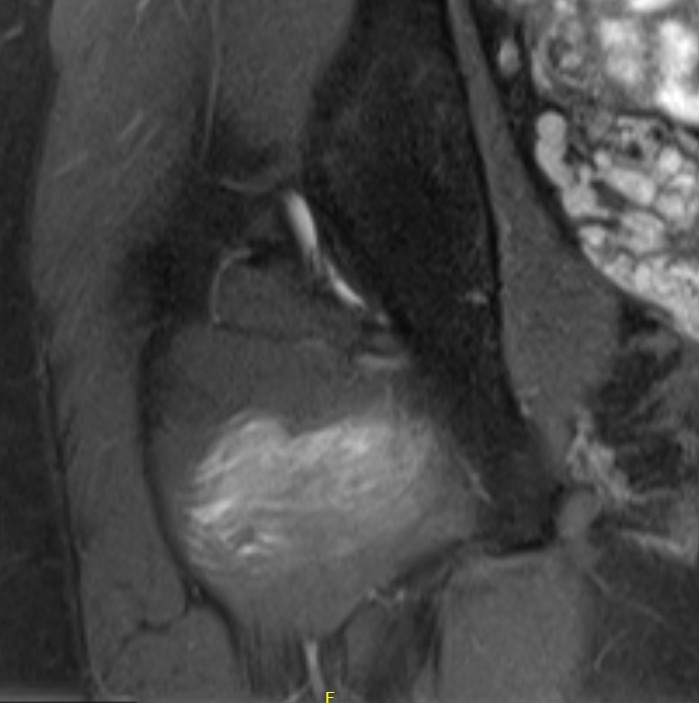

MRI

Reduced ischiofemoral space - distance between the lesser trochanter and the ischial tuberosity

Reduced quadratus femoris space - distance between hamstring tendon and iliopsoas

Inflammation / edema in quadratus femoris +/- fatty degeneration